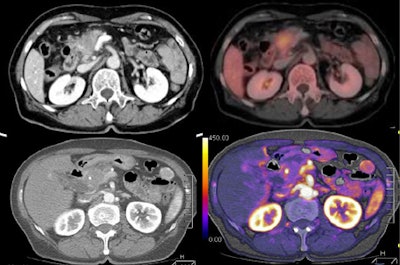

| Tumor and pancreas head are visible on tumor map, with PET image for comparison. All images courtesy of Dr. Sonja Kandel. |